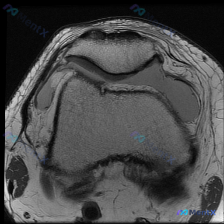

最近碰到一个有意思的读片病例,临床怀疑膝关节软骨异常,给了一张髌股关节轴位T1加权MRI,整理了一下分析思路分享给大家。 一、病例基本影像信息 这是单张膝关节髌股关节水平的轴位T1加权MRI扫描图: 1. 扫描层面:髌股关节水平,可见上方髌骨、下方股骨滑车沟的关节结构 2. 骨骼:股骨远端骨皮质完整...